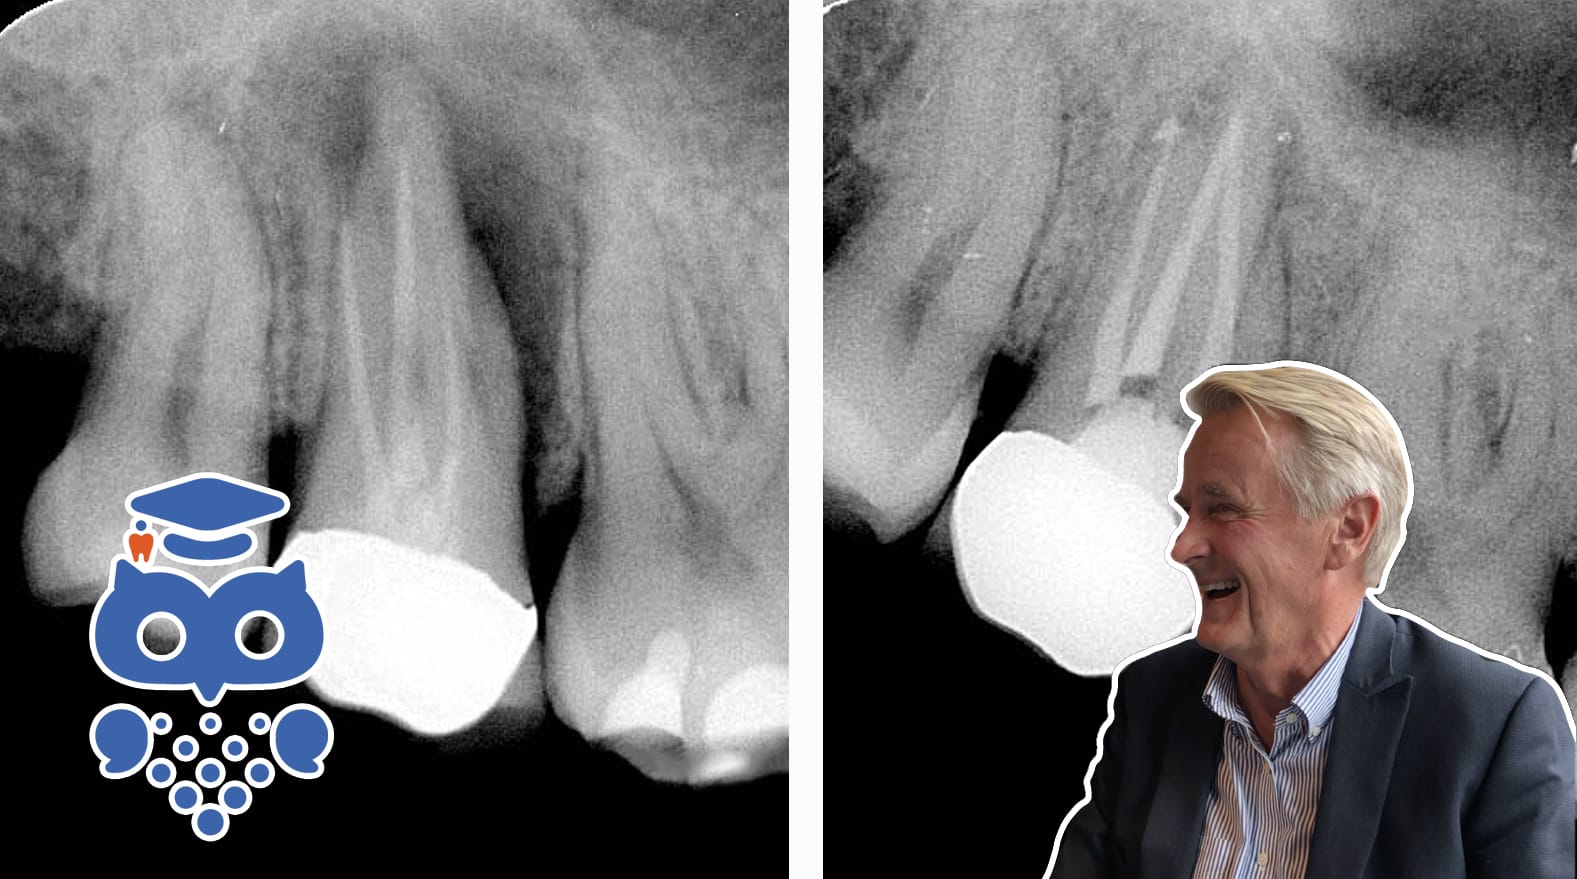

Rotfylld tand

Rotfyllning behandlar inflammerad eller infekterad pulpa för att förebygga apikal parodontit. Symtomfria rotfyllda tänder är vanliga, men komplikationer som smärta eller infektion kan uppstå. Prognosen är god, med 90 % överlevnad över 10 år, men risken för fraktur ökar med tandsubstansförlust.